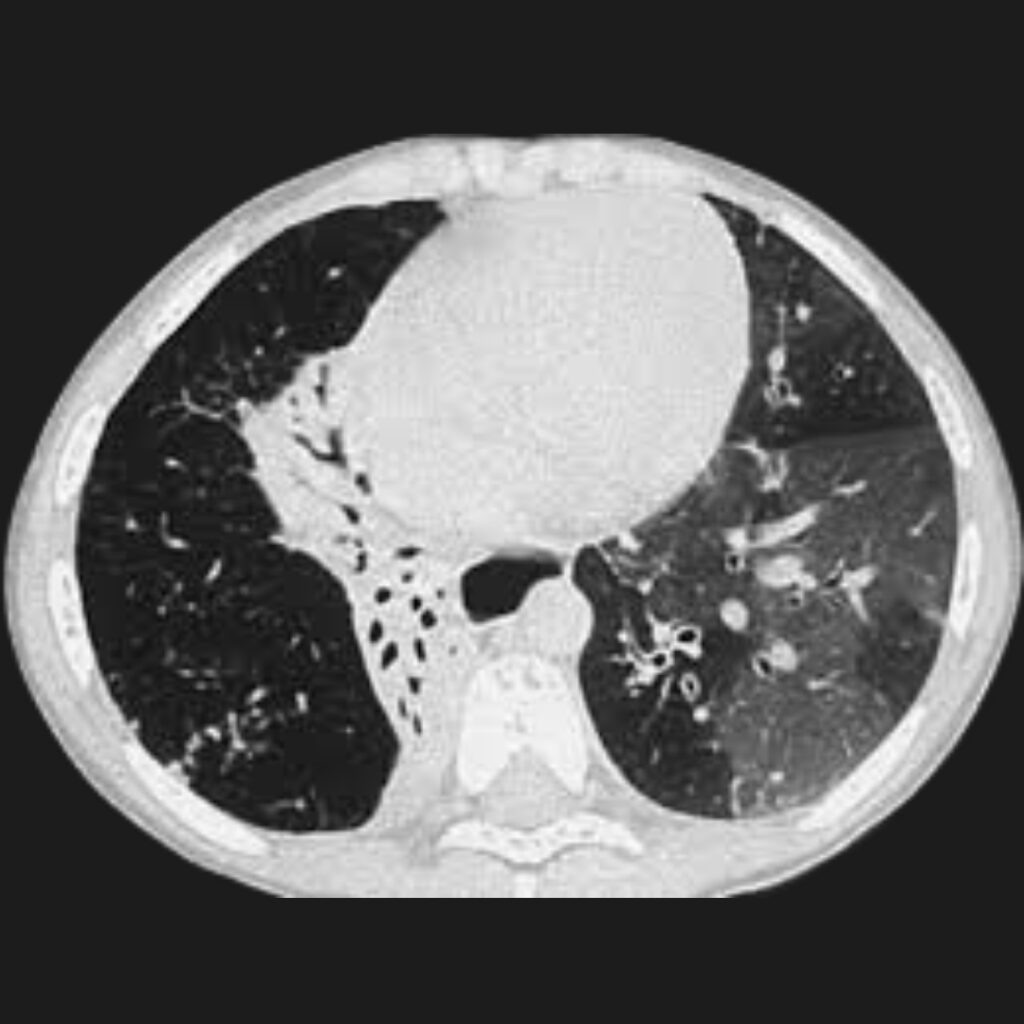

Tomografía computarizada de alta resolución: La tomografía computarizada de alta resolución es una herramienta fundamental en la evaluación de pacientes con sospecha de bronquiolitis obliterante postinfecciosa. Esta técnica permite obtener imágenes detalladas del parénquima pulmonar y de las vías aéreas pequeñas.

- Uno de los hallazgos más característicos es el patrón denominado mosaico de atenuación. Este patrón refleja la presencia de regiones pulmonares con diferente grado de ventilación. Las áreas que reciben menos aire aparecen más densas en las imágenes, mientras que las regiones hiperinsufladas se observan más radiolúcidas.

- Otro hallazgo frecuente es el atrapamiento aéreo, que se hace evidente especialmente durante las imágenes obtenidas en espiración. Además, pueden observarse bronquiectasias, que corresponden a dilataciones anormales de los bronquios, así como engrosamiento de las paredes bronquiales.